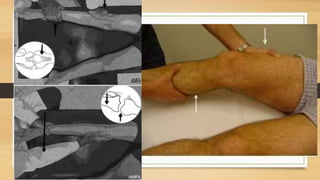

EXAMEN FISICO

EXAMENES AUXILIARES

Linea de Blumenssat,

cicatriz del cartílago

hialino

EXAMENES AUXILIARES Linea deBlumenssat, cicatriz del cartílago hialino